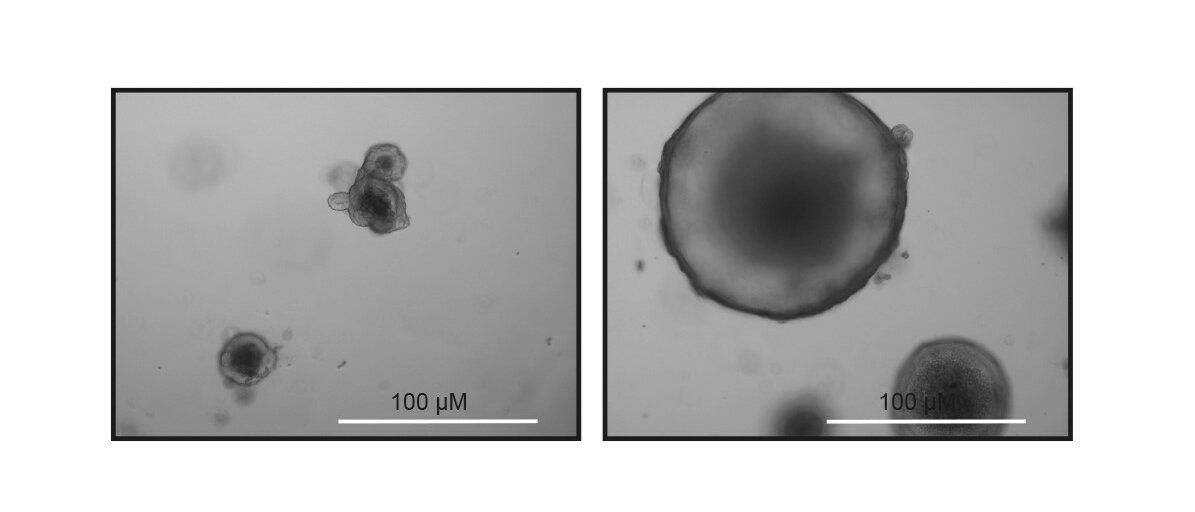

Nun ist mTOR kein Unbekannter in der Medizin. Der Datenweg wird schon länger für andere Krankheiten als therapeutisches Ziel genutzt – und das könnte einen frühen Zugang für die Krebstherapie bieten. Forscher haben bereits Mäuse und Zellsysteme im Reagenzglas, die erhöhte DNA-Schäden aufwiesen, mit Rapamycin behandelt, einem ganz spezifischen Hemmstoff des mTOR. Dadurch konnten die vermehrte Zellteilung und die daraus entstehenden Zellschäden deutlich reduziert werden.